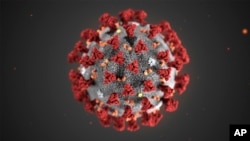

Novih 496 slučajeva koronavirusa, preminulo sedam pacijenata

Nacionalno koordinaciono tijelo za zarazne bolesti Crne Gore saopštilo je da je u posljednja 24 sata registrovano 496 novooboljelih od koronavirusa – što je do sada najveći dnevni zabeleženi porast broja oboljelih – dok je istovremeno prijavljeno sedam smrtnih ishoda.

Senad Begić, pomoćnik direktora Instituta za javno zdravlje, saopštio je da su u posljednja 24 sata laboratorije Instituta i drugih ustanova koje se bave PCR dijagnostikom analizirale 1299 uzoraka i registrovale 496 oboljelih, od kojih čak 225 iz Podgorice.

“Ovo je dnevni rekord kada se radi o broju novooboljelih od koronavirusa u Crnoj Gori”, rekao je Begić na konferenciji za novinare i dodao da će tokom večeri i jutra biti statistički obrađeno još blizu 500 urađenih testova, od kojih on očekuje “dobar dio novopozitivnih”.

Begić je novinarima rekao da “smo i mi i vi svjedoci da dešavanja na terenu apsolutno ne idu u prilog epidemiološke situacije, i za očekivati je da ovakvi brojevi budu još veći”.

“Ne vidim drugi izlaz iz ove situacije osim pooštravanja mjera… Očigledno da drugog izlaza nema ako dodje do eksponencijalnog rasta novooboljelih”, odgovorio je Begić na pitanje novinara i naveo da je do višestrukog dnevnog rasta došlo i u zemljama regiona, te da se i u regionu i u svijetu kreće sa pooštravanjem mjera.

“Imamo li šanse to da izbjegnemo, mislim da imamo, ali se plašim da smo zakasnili", rekao je Begić.

On je rekao da Podgorica, na osnovu sadašnjeg broja i trenda rasta novooboljelih, teško može izbjeći prelazak u "grupu tri" koja podrazumijeva zabranu rada kafića i zatvaranje škola, ističući da strahuje da bi glavni grad mogao preći u "grupu četiri" u kojoj se podrazumijeva i zabrana izlaska nakon 22 sata.

“Što se tiče broja preminulih, od posljednjeg presjeka do danas, prijavljeno je sedam novih smrtnih ishoda”, rekao je Begić i dodao da je nastariji preminuli pacijent imao 83 a najmlađi 60 godina.

On je naveo da je, obzirom da se u posljednja 24 sata oporavilo 240 pacijenata, trenutno 4.434 aktivnih slučajeva infekcije koronavirusom.

“Od početka dešavanja ukupno smo imali 19.210 oboljelih”, rekao je Begić.

Epidemija koronavirusa u Crnoj Gori je alarmantna, saopštili su tamošnji zdravstveni zvaničnici, i upozorili da će, kako su ukazali, neodgovorno ponašanje velikog broja građana imati nesagledive posljedice.